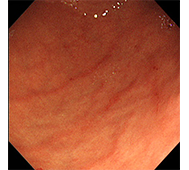

食道がん

初期症状は食道違和感や喉のつかえ感などの不定愁訴に近いため、発見が遅れやすく、食道がん自体がリンパ節転移が多いことや、周囲に浸潤しやすいことから、早く進行します。

早期がんの場合はそれに伴う身体所見はほとんどありません。